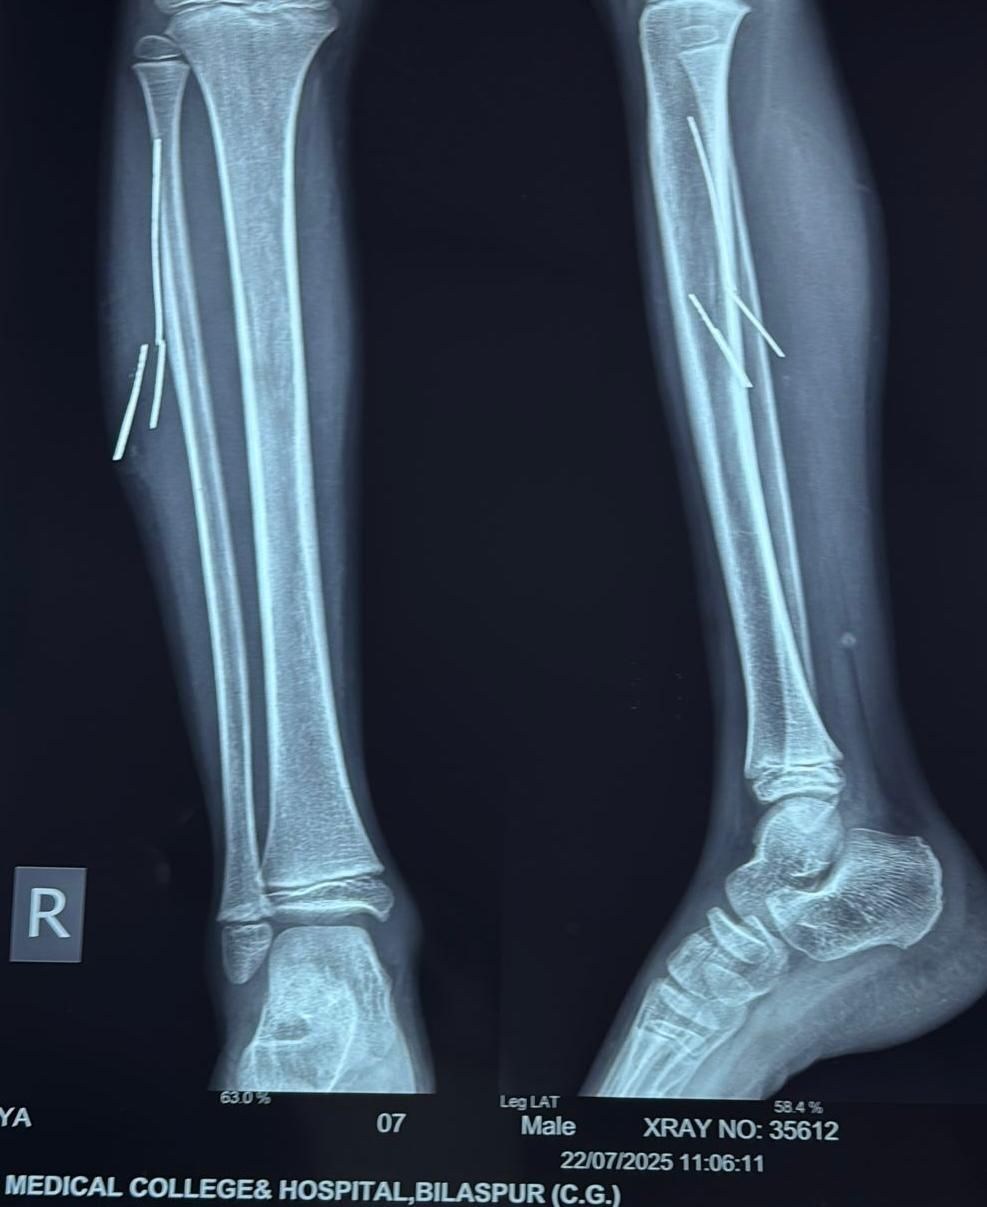

यहां सर्जन डॉ. बी.डी. तिवारी की टीम ने एक्सरे और सोनोग्राफी जांच कराई, जिसमें तार के चार टुकड़े (2 से 5 सेमी लंबाई के) पैर की मांसपेशियों में गहराई तक धंसे होने की पुष्टि हुई।

स्थिति की गंभीरता को देखते हुए सर्जन डॉ. ओ.पी. राज और डॉ. बी.डी. तिवारी ने ऑपरेशन का निर्णय लिया। लेकिन परंपरागत ऑपरेशन की तुलना में कम चीरा लगाकर तारों को निकालने की योजना बनाई गई। इसके लिए रेडियोलॉजी विभागाध्यक्ष डॉ. अर्चना सिंह के निर्देशन में डॉ. अमन अग्रवाल ने ऑपरेशन थिएटर में ही लाइव सोनोग्राफी कर लोकेशन चिन्हित की।

इस सटीक तकनीक की मदद से सर्जनों ने बिना मांसपेशियों को अधिक क्षति पहुँचाए तारों को निकाल दिया। ऑपरेशन के बाद बच्चा अब मेल सर्जरी वार्ड में तेजी से स्वस्थ हो रहा है।